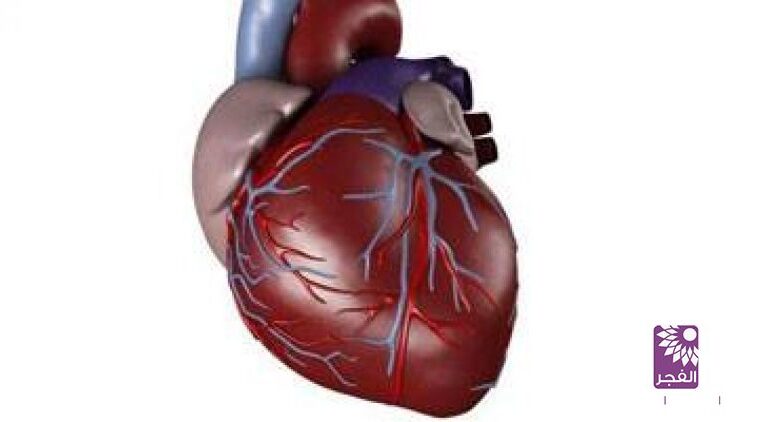

اكتشاف “بروتين” يساعد القلب فى ضخ الدم

تلفزيون الفجر الجديد| كشفت الدراسة العلمية التى أجراها البروفيسور الفرنسى “هوجو – آجويلانيو” عن الأمراض الناتجو عن الشيخوخة خاصة أمراض القلب فى ضخ كمية الدم اللازمة، لتلبية احتياجات الطاقة فى الجسم والتى تصيب مليون شخص فى فرنسا يعانون من عدم قدرة القلب على تقديم الدم اللازم للجسم.

وقد أجريت التجارب على مجموعتين من الفئران الشابة والعجوزة وقياس عملية سريان الدم لمدة أربعة أسابيع وقد توصلوا إلى وجود “بروتين” يعرف باسم “جى – دى – اف -11″ يشير إلى ارتفاع نسبة الدم لدى الفئران الشابة وعدم وجوده لدى الفئران العجوزة وعندما استطاعوا إعادة بناء أنسجة القلب.

وقد شجع ذلك العلماء على تجربة حقن هذا الهرمون على الإنسان فى غضون الخمس سنوات القادمة، كما أنه يلعب دورا هاما فى تقسيم الخلايا الجذعية.